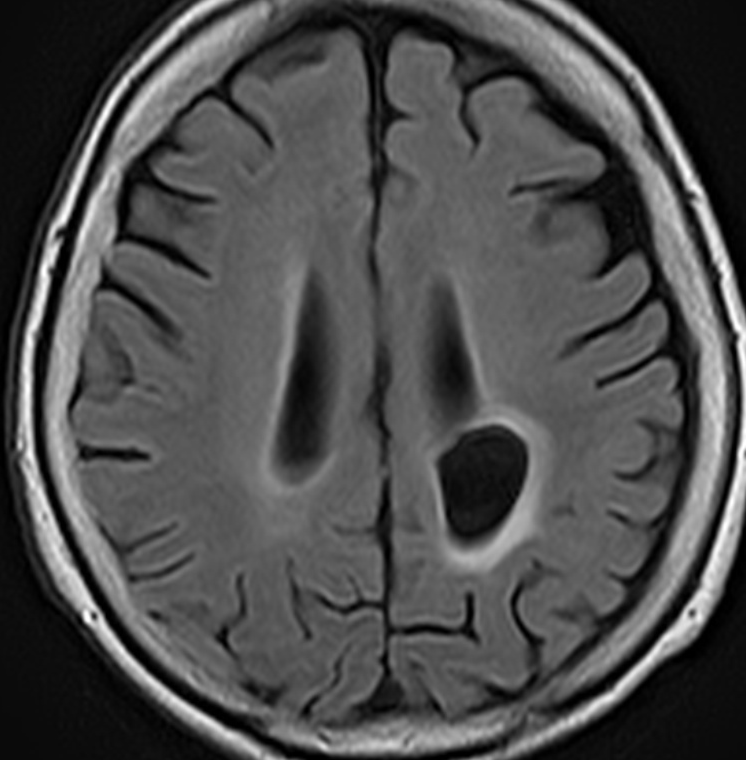

左は8歳時のMRIで,異常所見がありませんでした。左側頭葉に発作時の異常脳波所見が認められ,側頭葉てんかんの診断でカルバマゼピンの投与が開始されました。9歳時に精神症状を呈する発作となりレベチラセタムとゾニザミドが加えられました。右側のMRIは9歳時のものですが異常所見はありませんでした。前後にさまざまな画像が撮影されていましたが脳腫瘍の所見はありませんでした。

11歳時のMRIで側頭葉下面に異常所見が出現しました。